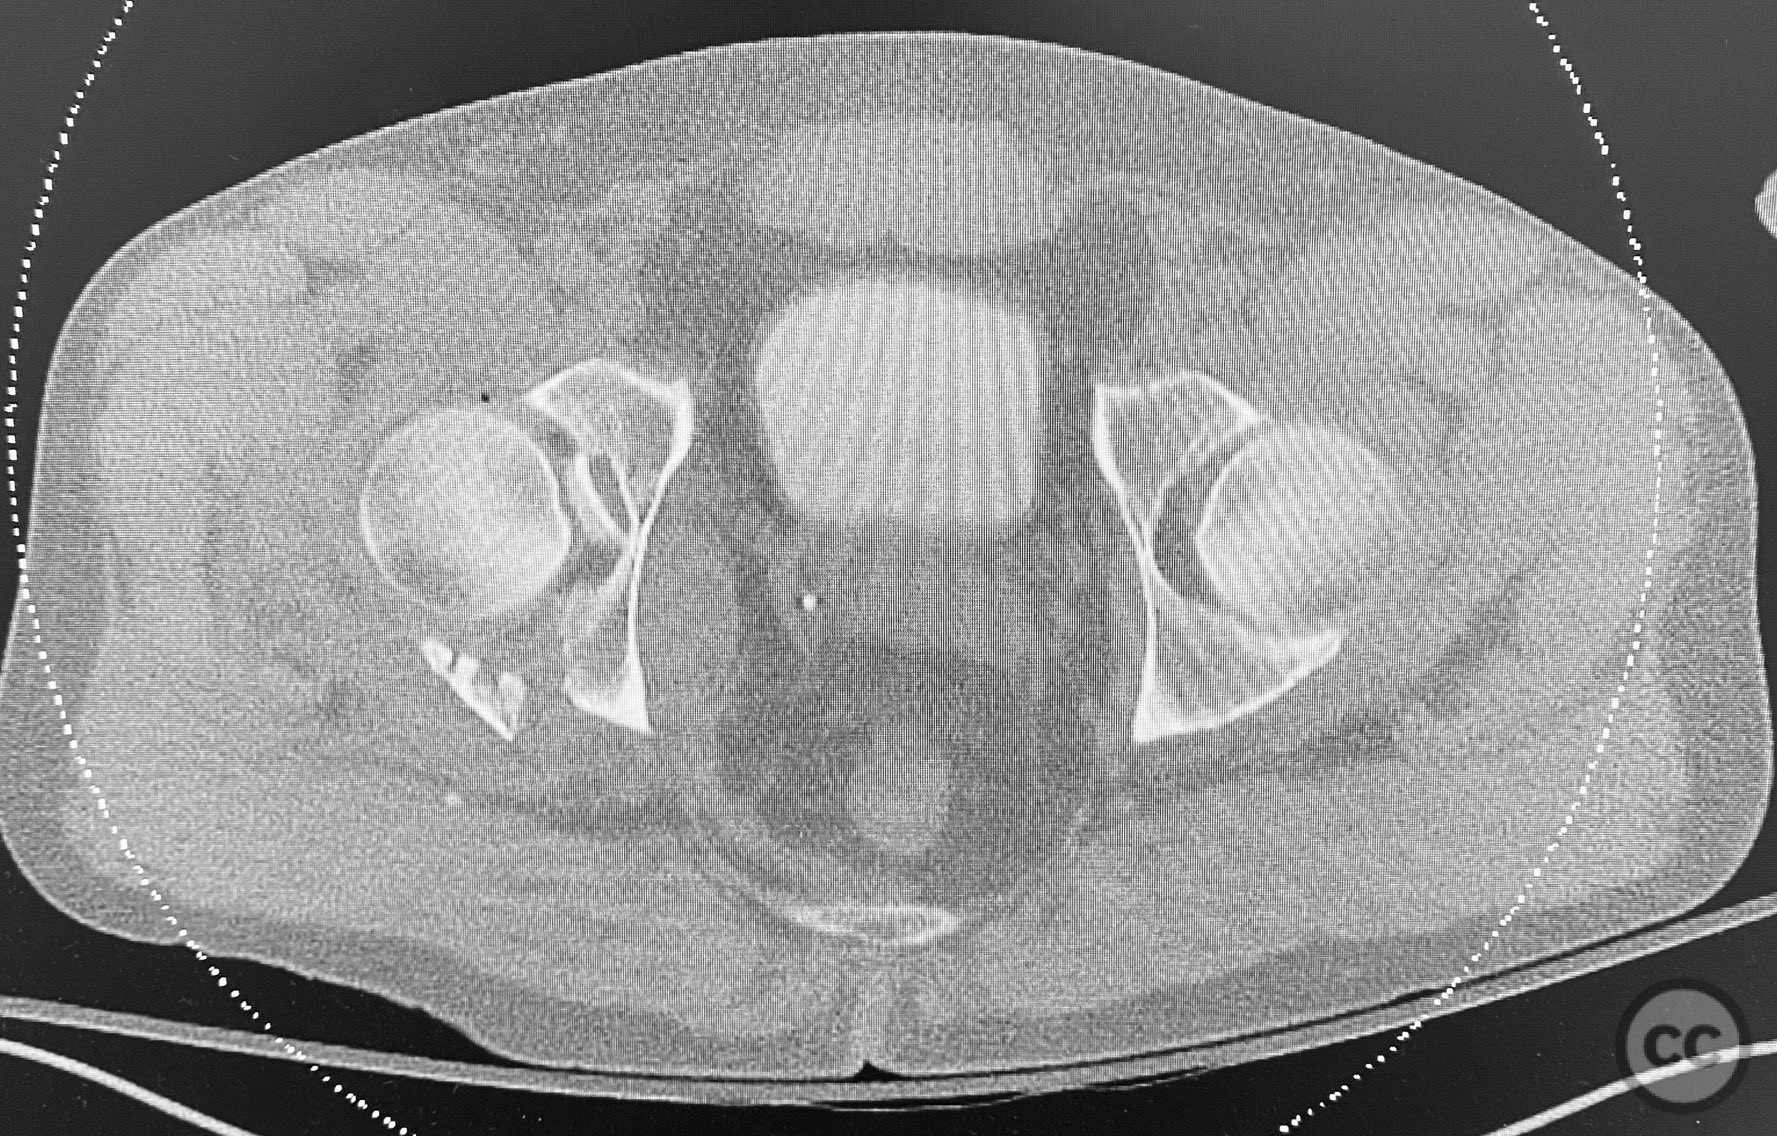

Early Percutaneous Stabilization of Complex Pelv...

Combined Bilateral Sacroiliac Disruption and Tra...

Posterior Wall Acetabular Fracture-Dislocation w...

Complex Acetabular Posterior Wall and Transverse...

Complex Both Column Acetabular Fracture with Dom...

Posterior Medial Dome Impaction in Associated Ac...

Combined Anterior Column and Posterior Hemi-Tran...